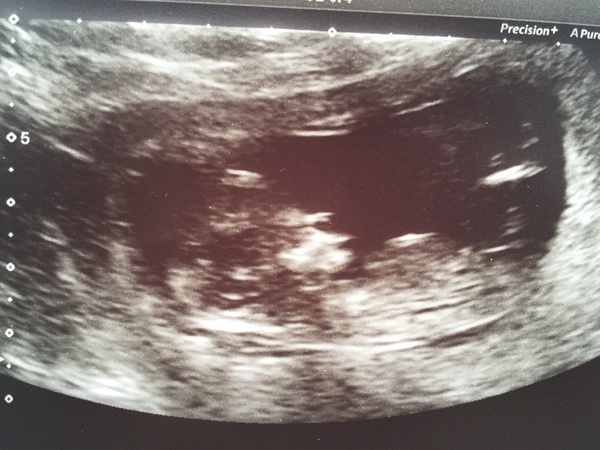

Had our 12 week scan today... saw a very wriggley little bean Grin feeling over the moon after a weekend of worry, a hospital visit, and the Dr telling me to bed rest Grin

I've been pretty quiet up till now. Possibly cos I didn't quite believe it was happening. Lol! Anyway, had my first scan yesterday and got dated at 12+2 so I was only a day out.

Booked in for another scan today....i know I really need to get a grip and stop booking these scans! Anyway scan was great, baby lying with his hands behind his head!! Amazing to see how chilled out he is in there!!!

Scanner guessed a boy although still slightly too early to tell - gender scan booked for the 17th of this month!

Hey everyone! So glad to hear about your scan Moose. Lovely to hear about and see all of the other scan pics too. Got our downs/Edwards/Pataus and we are classed as low risk so relieved about that. 13+4 today and feeling horrendously bloated. Is anyone else just feeling so round and sluggish? All I'm doing is eating and I feel like a total slob. Working really long hours and just can't get motivated to be active. Need to give my head a shake and sort it out! Sorry for the moan! Hope you're all well x